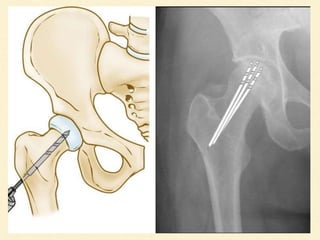

CORE DECOMPRESSION

Treatment of choice for

Ficat and Arlet I,IIA

reversible etiology

Simple to perform , very low complication

More effective than nonoperative treatment of early

Osteonecrosis of femoral head

Reduce the intraosseus pressure in the femoral head

Restore Normal vascular flow

Subsequently alleviate the pain in the hip

CORE DECOMPRESSION Treatment ofchoice for Ficat and Arlet I,IIA reversible etiology Simple to perform , very low complication More effective than nonoperative treatment of early Osteonecrosis of femoral head

CORE DECOMPRESSION Reduce theintraosseus pressure in the femoral head Restore Normal vascular flow Subsequently alleviate the pain in the hip